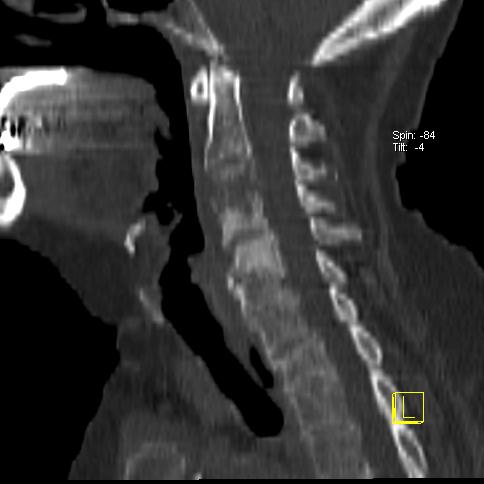

Métastase mixte cervicale d’un cancer du rein

Patiente de 60 ans, bilan d’extension osseux d’un cancer du rein droit

Corps Entier: hyperfixation intense hétérogène sur le rachis cervical associé à une hyperfixation sur le rachis lombaire et sur l’aile iliaque droite

Tomoscintigraphie couplée au TDM: hyperfixation sur la partie condensante de la lésion métastatique mixte (lytique et condensante) touchant les corps vertébraux de C3 et C4 et l’apophyse transverse gauche de C3. Atteinte du mur postérieur, risque de compression médullaire, avis neurochirurgical en urgence.